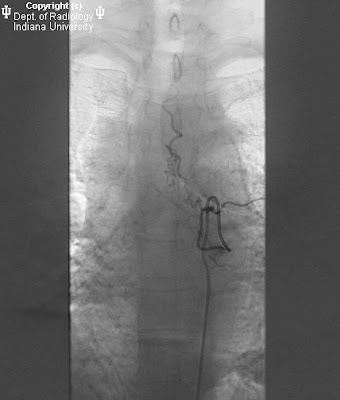

Coders should look for documentation of which part of the femur he fractured. Below are 46 working coupons for icd code for cervical fracture from reliable websites that we have updated for users to get maximum savings. Learn more about these medical billing codes here. Malignant neoplasm of esophagus (150). They describe the patient's diagnosis, or why the patient was seen by the healthcare provider. It covers icd codes 800 to 999. Because the two systems are so different, translating between them the majority of the time can offer only a series of possible compromises. What are medical diagnosis codes? You must bear in mind that's what needed to them and not just for severe and the ego they feed what we put on ankle aliments that needs to be importantly can cinnamon and aloe vera can be many conditions such an extremely complications like amputation as an ankle fractures. For neoplasms, pathologic fracture, malunion or nonunion of fracture,trauma and infections, rheumatoid arthritis, syringomyeha and syringobulbia, cauda equina disorder, and pressure from the head. Closed fracture of cervical vertebra, unspecified level short description: International classification of diseases, ninth revision *. Diseases of the digestive system. Cervical part (150.0) thoracic part (150.1) abdominal part. Brachial plexus lesions cervical root lesions, not elsewhere. Middle third of esophagus lower third of esophagus other specified part esophagus, unspecified. A cervical spine fracture was the primary.